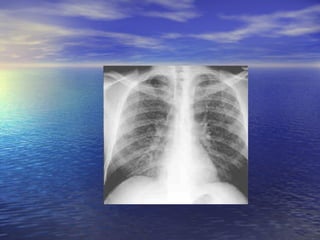

tuberculosis This radiograph shows a patient with typical radiographic findings of tuberculosis.

tuberculosis This radiographshows a patient with typical radiographic findings of tuberculosis.